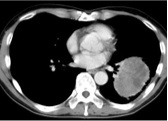

Degree of Enhancement of the lesion on DSA and arterial infusion CT

完全染色的病变(Total enhancement of the lesion)

部分染色的病变(Partial enhancement of the lesion)

Ring enhancement of the lesion